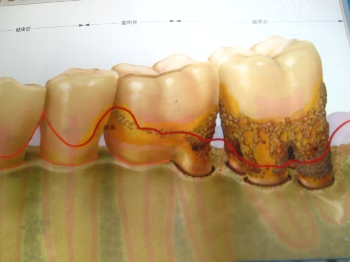

それでは、正しい方程式は、

歯周病=歯肉+歯槽骨+歯根膜+α

(・_・o)ン? (o・_・)ン? (o・_・o)ン?

という皆様の顔が浮かんできますねぇ(*^^*ゞ

歯周病は呼んで字の如く、歯の周りの病気です。

したがって歯の周りにある組織はなんなのか?を考えていかないと歯周病を予防することはできません。